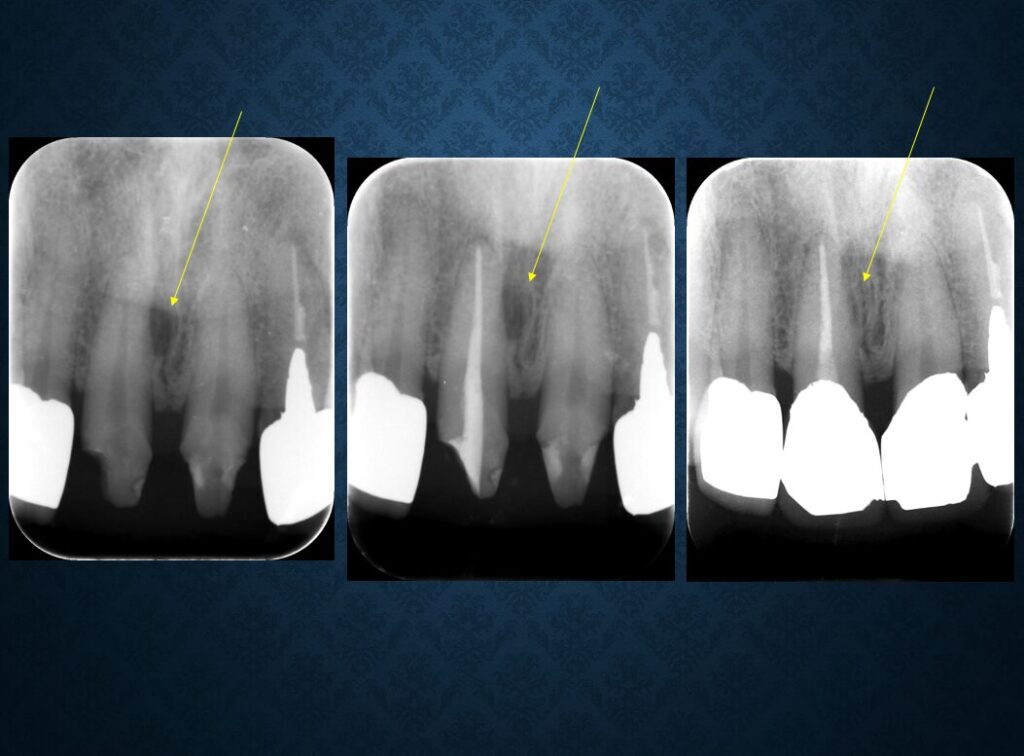

40代フィリピン人男性の方でした。欠損部には入れ歯が入っていました。インプラントに代えて欲しいというご希望でした。職業は会社経営、モデル、英会話教師、ボディービルダー、六本木警察フィリピン語講師、映画俳優など多岐にわたり、日本だけでなく、オーストラリア、台湾、スペインなどを渡り歩いている方でした。多忙を極めていらしたので治療は度々中断しましたが、無事にゴールできました。